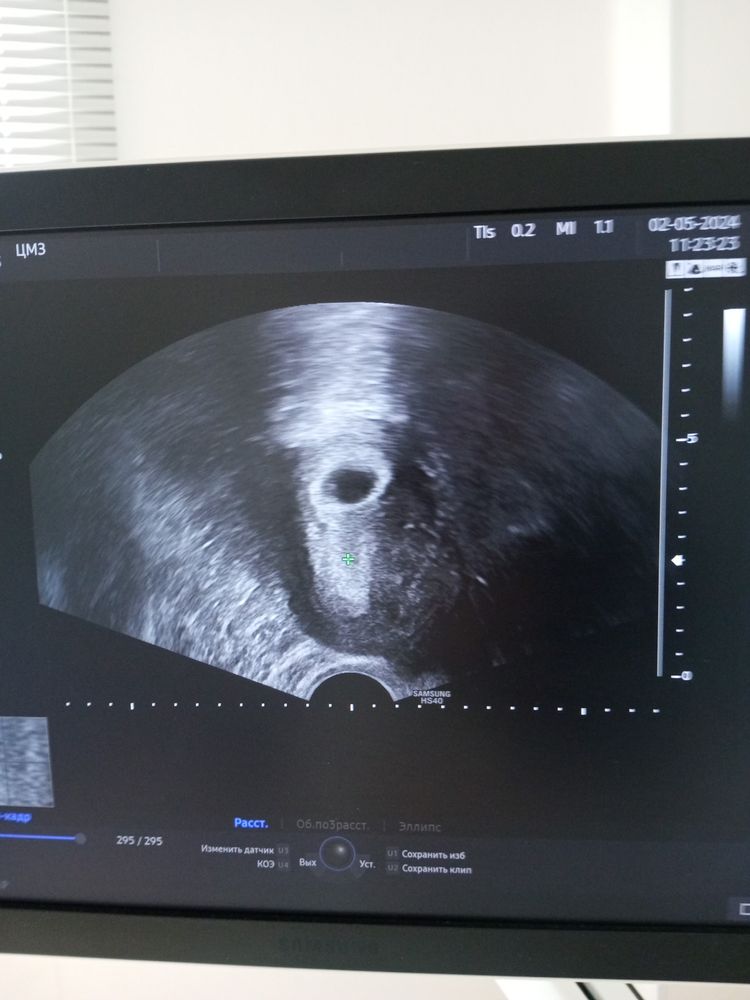

Елена в ЭКО-мама 2 года УЗИ 23ДПП. Результаты УЗИ Сделала сегодня УЗИ, прижился 1 малыш🩷есть пульсация 🩵 На 8 мая опять ре записала Посмотрите еще 20 записей на эту тему Отменить Ответить Виктория Получается на 23 дпп все увидели и эмбрион и сердцебиение? У меня тоже на 23 день узи будет))) 02.05.2024 Ответить Елена Виктория , ре сказала есть пульсация, полноценно ❤ 8 будет дай Бог 😇🙏👼 02.05.2024 Ответить Алина Тоже сегодня 23 дпп, но УЗИ на 30 дпп назначили) лёгкой Вам беременности и родов) 02.05.2024 Ответить Елена Алина, спасибо и Вам всего самого 🫸🫷 02.05.2024 Ответить Алина Елена, токсикоз ещё не начался?) 02.05.2024 Ответить Елена Алина, ой, не пойму он не он -тошнит, как будто слабость, без рвоты и синусит мучает 02.05.2024 Ответить 18 дпп. Повторное УЗИ Узи на 24 дпп 5 дневки ( 6.1 акушерские недели).... Кажется все идёт не так гладко (( Чаты Беременных Выберите чат: Январята-2026 Февралята-2026 Мартята-2026 Апрелята-2026 Майчата-2026 Июнята-2026 Июлята-2026 Августята-2026